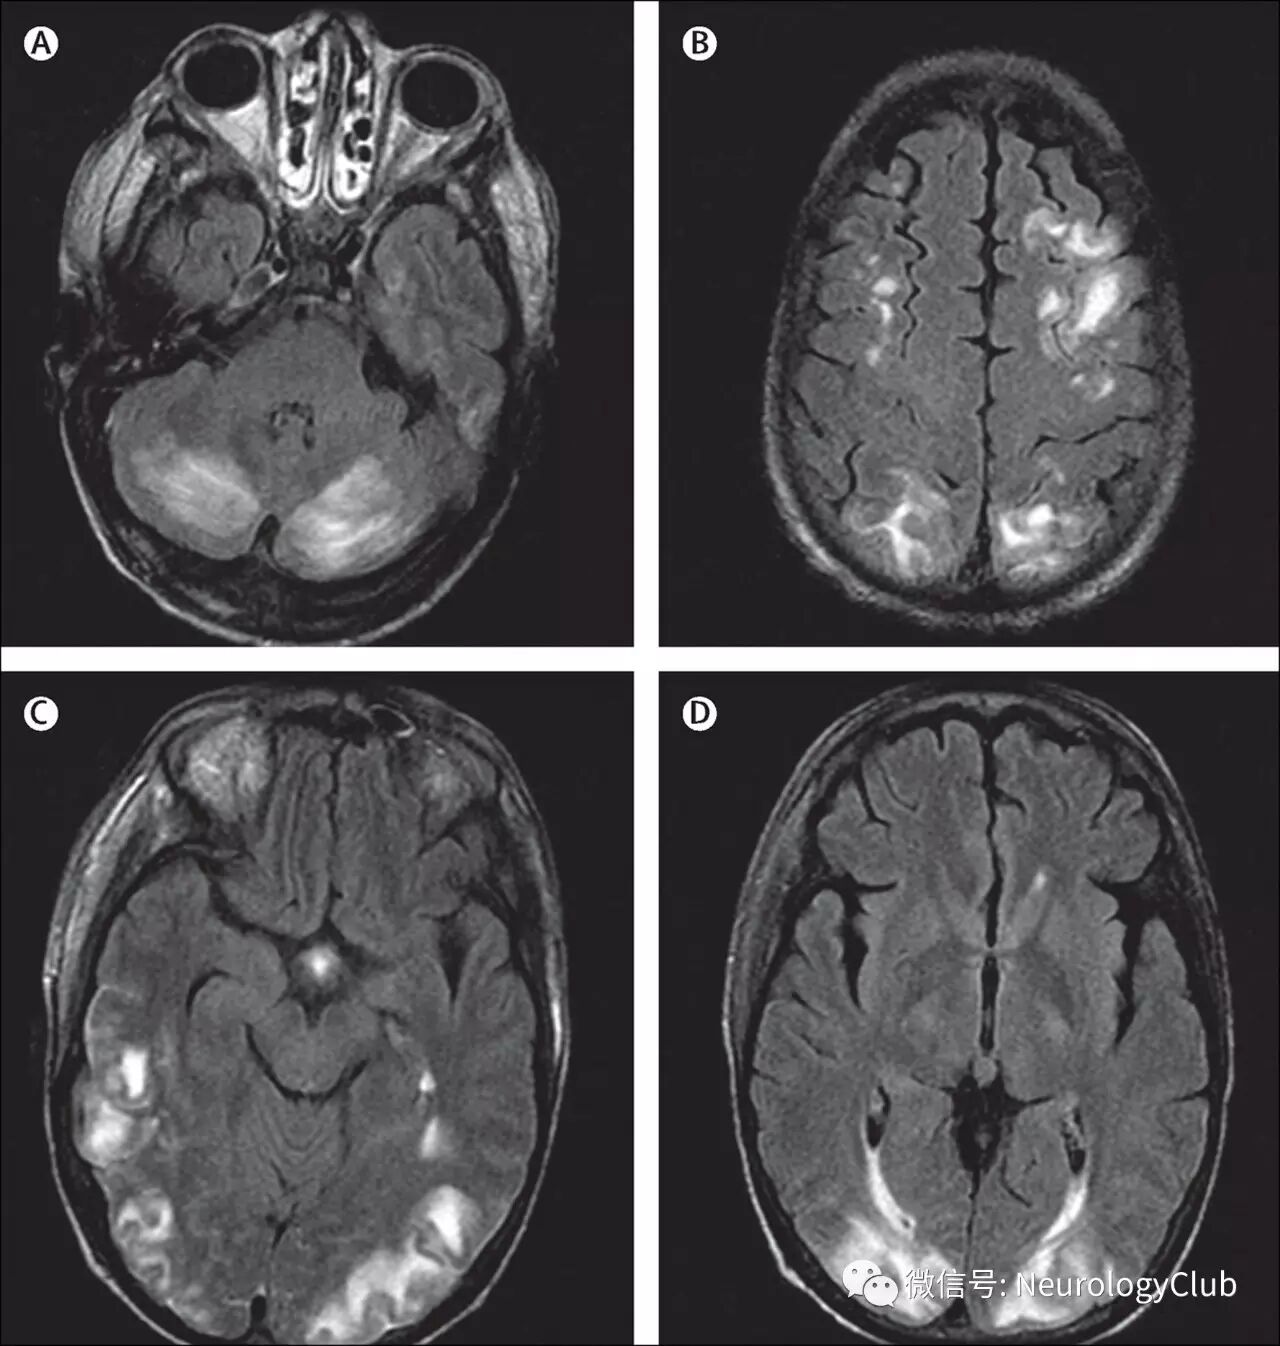

颅脑影像学有助于诊断PRES以及鉴别诊断。血管源性水肿可以通过CT来发现,但颅脑MRI更敏感。由于缺乏诊断金标准,无法评估MRI的特异性。颅脑MRI典型表现为双侧顶枕叶为主的血管源性水肿,呈T1低信号,T2/FLAIR高信号,DWI等或低信号,ADC高信号。通常累及皮质下白质,较少累及皮质。水肿几乎累及双侧,不完全对称。

(图2:典型的黑水像PRES影像学表现)

影像学表现可分为四型:顶枕型,全脑分水岭型,额上回型和中央变异型。影像学分型和水肿严重程度都不与临床表现分型和严重程度相关。额叶和颞叶受累者约占75%。累及基底节和脑干者有1/3,累及小脑者约占半数。这些部位的水肿一般是伴随着顶枕部位的受累。病变不累及顶枕区域者少见。仅累及单侧大脑和孤立性脑干与小脑水肿者需要排除其它疾病。

(图3:均为黑水像;A-C:顶枕型PRES;D-F:全脑分水岭型PRES;G-I:额上回型PRES)